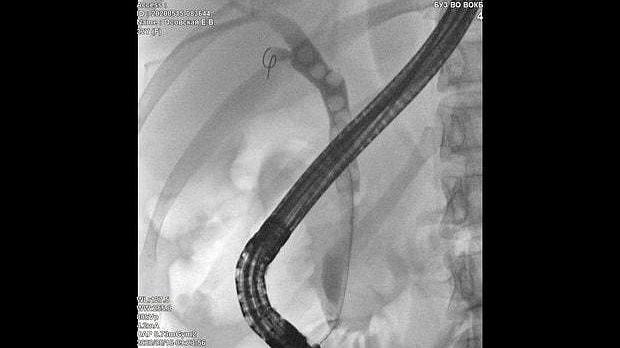

Здравствуйте. Пациентка, 32 года. Поступила на хирургическое отделение с диагнозом ЖКБ: холедохолитиаз. По данным МРТ: ЖКБ, множественные мелкие конкременты холедоха. При дуоденоскопии выявлено наличие вклиненного конкремента большого дуоденального сосочка. Выполнена прекатсфинктеротомия, получено 3 конкремента, диаметром около 0.4-0.5 см. Далее канюляция холедоха проволочным папиллотомом, выявлены многочисленные конкременты холедоха. Выполнена литоэкстракция ревизионным баллоном (на последнем фото окклюзионная холангиография - в просвете холедоха не конкременты, а пузырьки воздуха)).